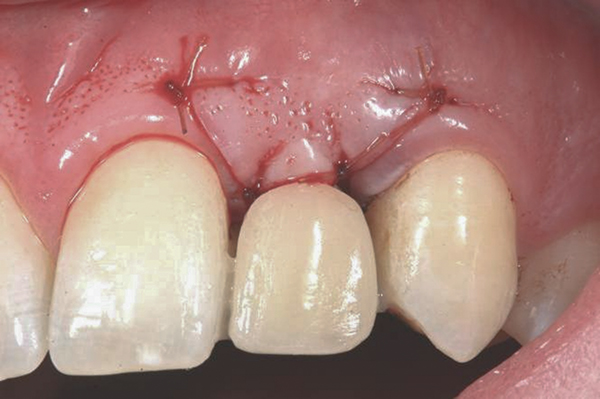

In the esthetic zone it is preferable to avoid elevating papillae because flap elevation may induce recession and create unesthetic black triangles.4 If a flap is necessary to perform a procedure in an edentate area when adjacent teeth are present, the following technique can be used to circumvent blunting papillae. Make a horizontal incision along the midcrestal or palatal aspect of the ridge and terminate the incision 1 mm from the adjacent teeth (Figure 1). The incision is created palatally if it is desired to transpose keratinized tissue to the buccal. From the horizontal incision, create bilateral buccal vertical releasing incisions that extend obliquely at an angle (Figure 2). The vertical incisions can also be extended palatally (for access), but this is not always necessary (Figure 3). Preserved papillae contain gingival supracrestal fibers that subsequently help maintain papillary height (Figure 4). The distance the incision is extended vertically on the buccal is dictated by the task to be accomplished (eg, implant insertion only requires short vertical incisions, while bone grafting needs longer incisions) (Figure 5 and Figure 6). At the end of the surgical procedure, the severed papillary segments are sutured to their retained counterparts (Figure 7 and Figure 8). Figure 1 through Figure 8 demonstrate a submerged implant protocol.

Fig 7. Vertical releasing incisions sutured to attain primary closure, buccal view.

Figure 7

Fig 17. Vertical and horizontal incisions were sutured to attain primary closure.

Figure 17